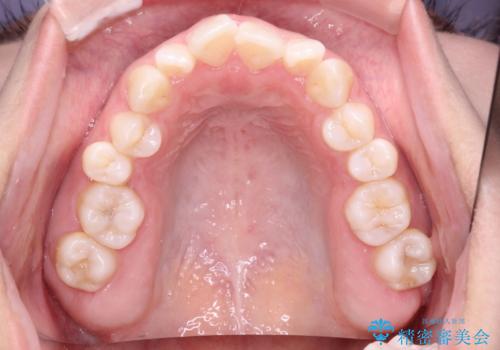

使用したマウスピース枚数は、30枚+14枚+11枚(初回マウスピース+リファインメント 2回、1週間に1枚交換ペース)

インビザライン治療により、捻転を含む歯列もしっかりと改善しています。

基本的な不正咬合部分は初回の30枚のマウスピースでほぼ改善しており、リファインメントでは前歯部の細かな調整など、患者様の要望を取り入れる形でシミュレーションをセットアップし、満足の行く結果に仕上がりました。